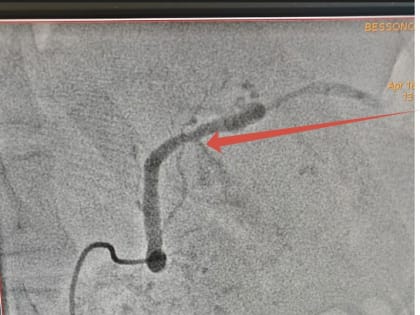

Врачи ЛОКБ впервые прооперировали липчанина  с внутренним кровотечением из крупной селезеночной артерии

Вчера в Липецкой областной клинической больнице успешно проведена внутрисосудистая операция по купированию внутреннего кровотечения из крупной селезеночной артерии.

Липецкие хирурги за 6 часов операции спасли пациента с внутренним кровотечением

Полина Трофимова Сейчас липчанин находится в реанимации Фото: ГУЗ "Липецкая областная клиническая больница" Рентгенэндоваскулярные хирурги Липецкой областной клинической больницы спасли жизнь 52-летнего пациента